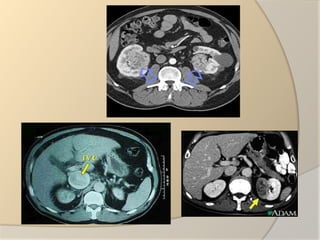

DIAGNOSISPhysical examination:FeverHigh blood pressureLab tests: Complete blood countUrinanalysisSerum calciumImaging tests:Ultrasound abdomen Abdominal CT scanMRI scanPET scanRenal angiographyIntravenous pyelogramChest x rayBone scanBiopsy          Fine needle aspiration          Core needle biopsy

DIAGNOSISPhysical examination:FeverHigh bloodpressureLab tests: Complete blood countUrinanalysisSerum calciumImaging tests:Ultrasound abdomen Abdominal CT scanMRI scanPET scanRenal angiographyIntravenous pyelogramChest x rayBone scanBiopsy Fine needle aspiration Core needle biopsy